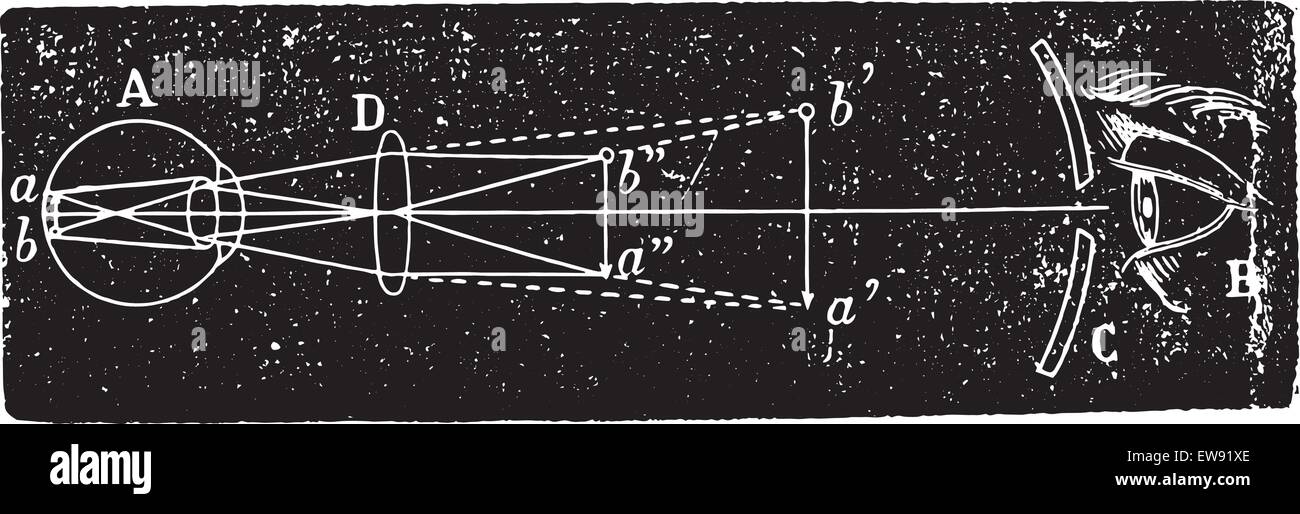

Engraving depicting an ophthalmoscope in use. Ophthalmoscopy, also called funduscopy, is a test that allows a health professional to see inside the fundus of the eye and other structures. The ophthalmoscope was invented by Hermann von Helmholtz (1821-1894) a German physician and physicist. Dated 19th century Stock Photohttps://www.alamy.com/image-license-details/?v=1https://www.alamy.com/engraving-depicting-an-ophthalmoscope-in-use-ophthalmoscopy-also-called-funduscopy-is-a-test-that-allows-a-health-professional-to-see-inside-the-fundus-of-the-eye-and-other-structures-the-ophthalmoscope-was-invented-by-hermann-von-helmholtz-1821-1894-a-german-physician-and-physicist-dated-19th-century-image186347727.html

Engraving depicting an ophthalmoscope in use. Ophthalmoscopy, also called funduscopy, is a test that allows a health professional to see inside the fundus of the eye and other structures. The ophthalmoscope was invented by Hermann von Helmholtz (1821-1894) a German physician and physicist. Dated 19th century Stock Photohttps://www.alamy.com/image-license-details/?v=1https://www.alamy.com/engraving-depicting-an-ophthalmoscope-in-use-ophthalmoscopy-also-called-funduscopy-is-a-test-that-allows-a-health-professional-to-see-inside-the-fundus-of-the-eye-and-other-structures-the-ophthalmoscope-was-invented-by-hermann-von-helmholtz-1821-1894-a-german-physician-and-physicist-dated-19th-century-image186347727.htmlRMMR4TBY–Engraving depicting an ophthalmoscope in use. Ophthalmoscopy, also called funduscopy, is a test that allows a health professional to see inside the fundus of the eye and other structures. The ophthalmoscope was invented by Hermann von Helmholtz (1821-1894) a German physician and physicist. Dated 19th century